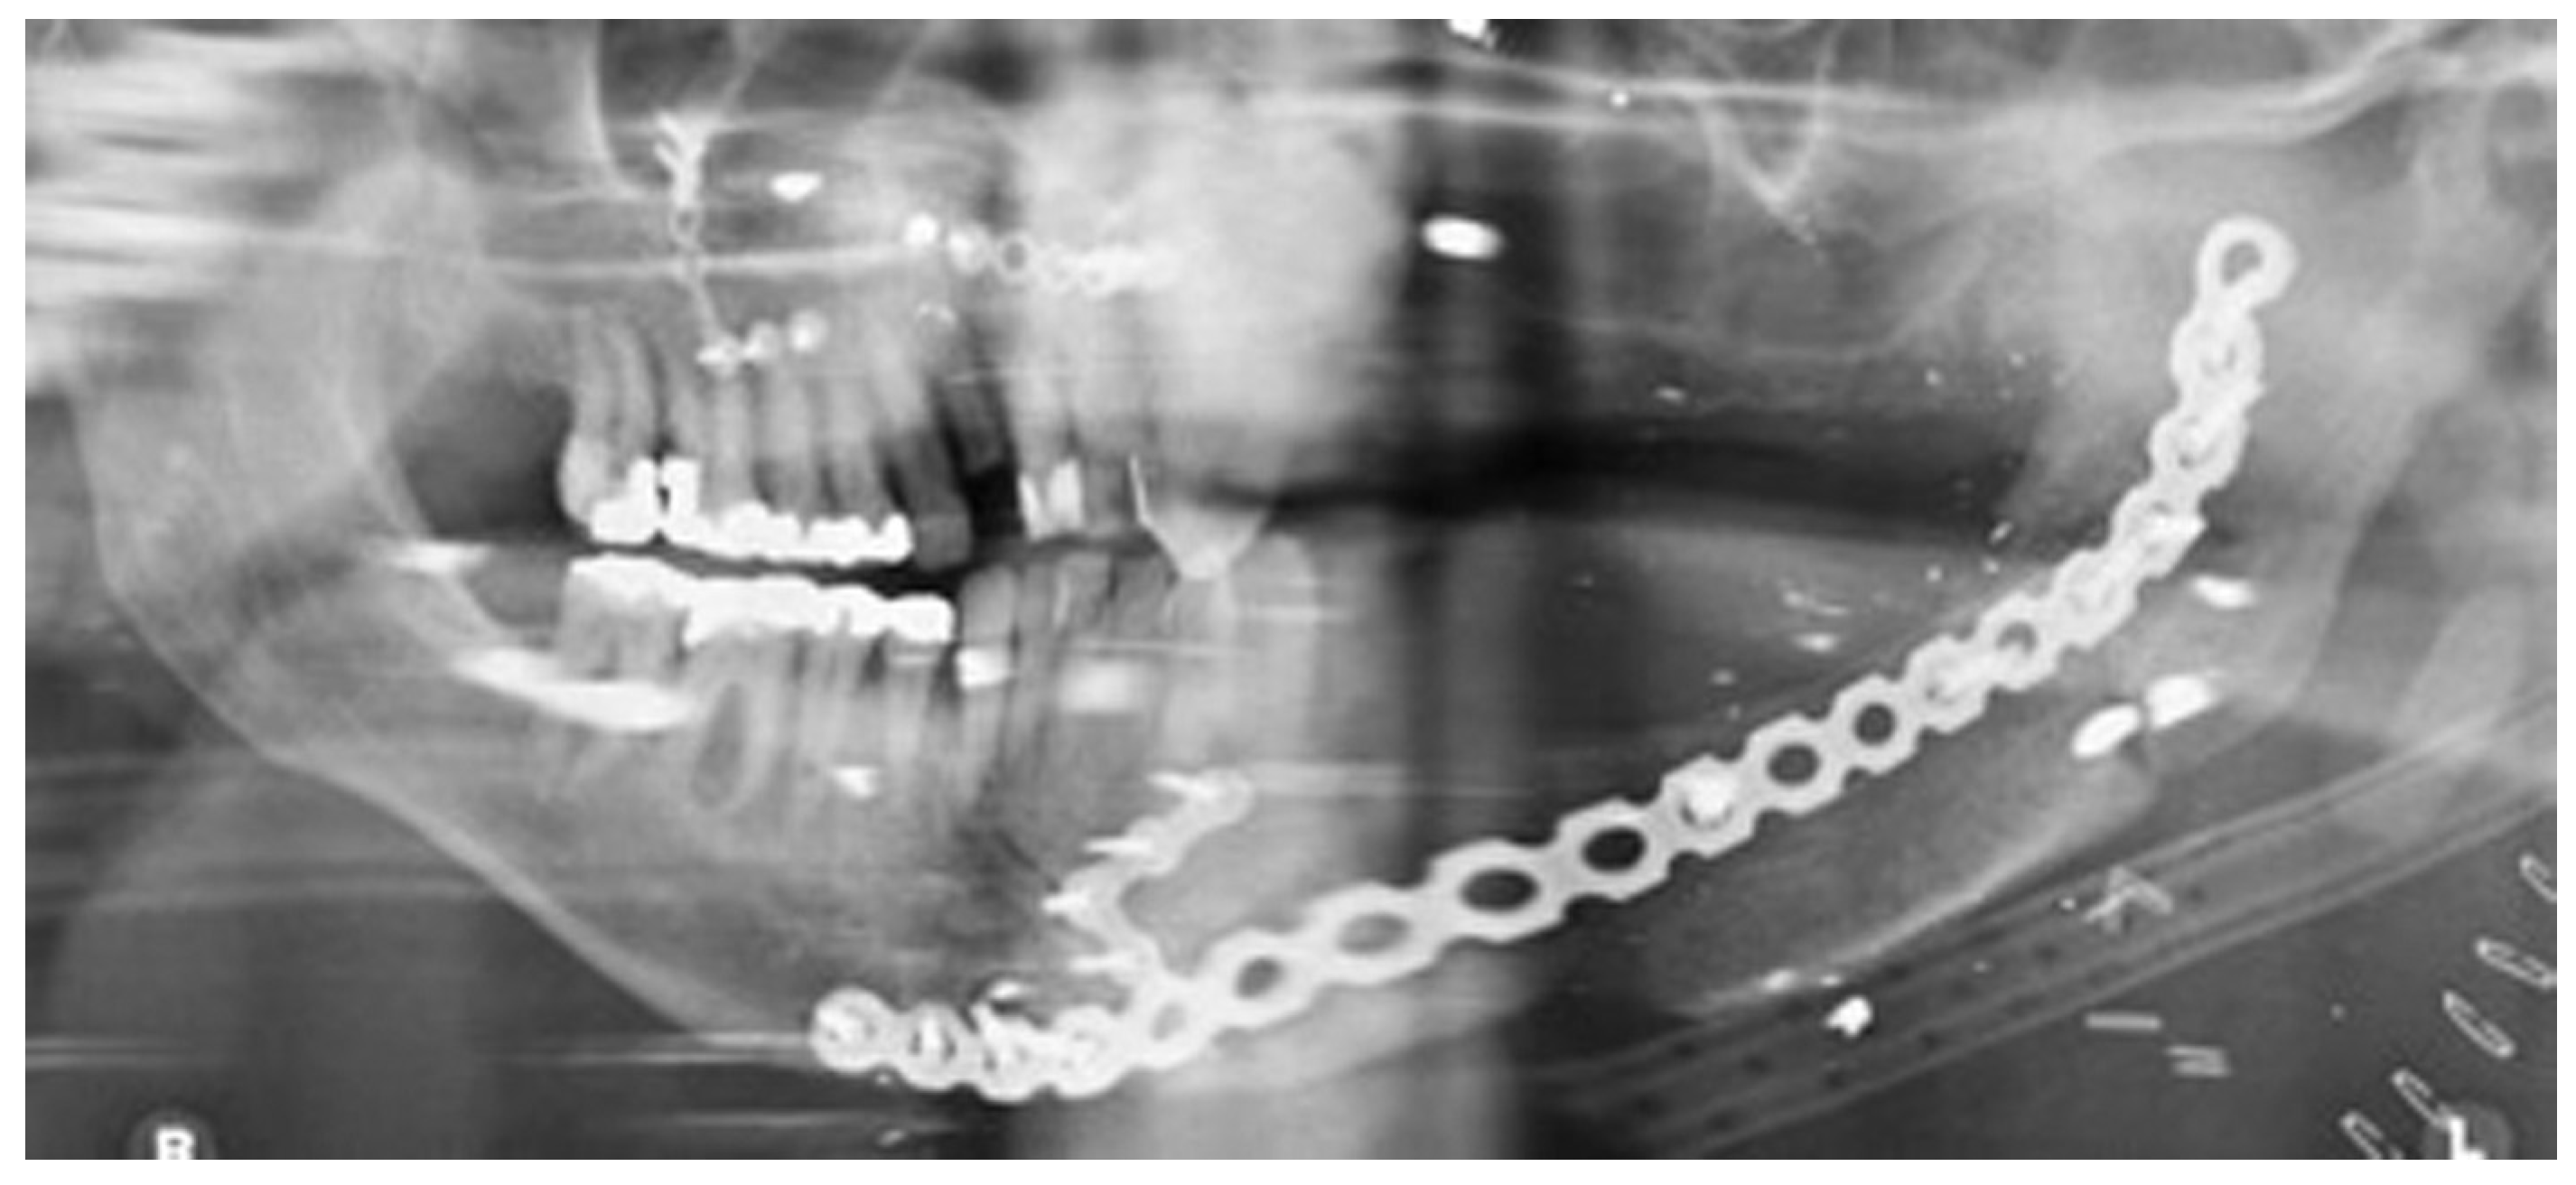

Figure 11.

Orthopantomography(OPT) showing free bone graft placed in segmental defect.